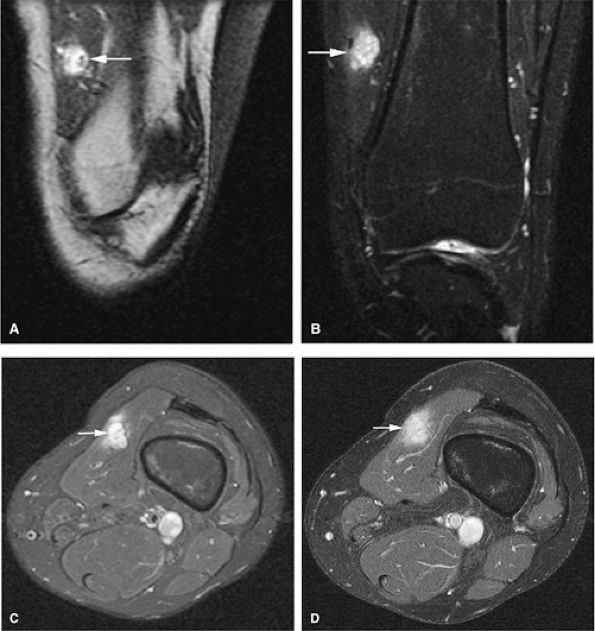

Epiphyseal and metaphyseal marrow edema associated with periosteal reaction is a frequent finding, seen in up to 57% of cases of long-bone involvement.67 MR imaging is sensitive to this extensive reactive marrow edema, which demonstrates decreased signal intensity on T1-weighted images and increased signal intensity on T2-weighted or STIR images.

Fluid–fluid levels can be seen in chondroblastomas.53

FIGURE 14-34 ● Extensive marrow edema (arrowheads) in reaction to an epiphyseal-based chondroblastoma of the tibia (arrows) demonstrates low signal intensity on a coronal T1-weighted image (A) and hyperintensity on a coronal STIR image (B). Axial STIR image (C) demonstrates fluid–fluid levels within the lesions (arrow). (D) A coronal CT image shows a well-defined lytic defect in the tibial plateau (arrow). (E) An axial CT image obtained during radiofrequency ablation of the tumor shows the radiofrequency probe (arrow) within the chondroblastoma.